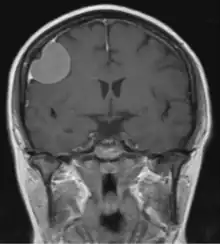

Dural tail sign seen associated with a meningioma

The dural tail sign (also known as "dural thickening", "flare sign", or "meningeal sign") is a radiological finding observed in magnetic resonance imaging (MRI) studies of the brain that refers to a thickening of the dura mater immediately adjacent to a mass lesion, such as a brain tumor.[1] Initially, the dural tail sign was thought to be pathognomonic of meningioma, a slow-growing tumor that arises from the meninges.[1] However, subsequent studies have shown that it can also be observed in various intra- and extra-cranial pathologies and in spinal lesions.[1] It is not a completely sensitive finding, as it is seen in only 60-72% of cases.[2] It is not completely specific either, as it has been described associated with lesions like neuromas, chloromas, pituitary diseases, granulomatous disorders, cerebral Erdheim-Chester disease, lymphomas, metastasis, hemangiopericytomas, schwannomas, and gliomas such as glioblastoma multiforme (GBM).[2][3] The final diagnosis should be further established through cerebrospinal fluid analysis or histopathological examination following a biopsy.[3]